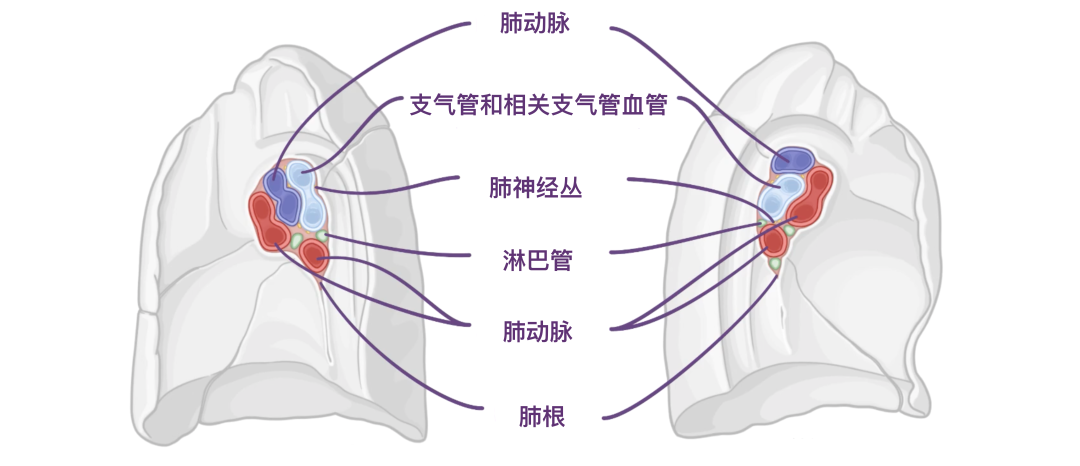

肺通过肺根与纵隔相连,由支气管和相关支气管血管、肺动脉、上肺静脉和下肺静脉以及肺神经丛和淋巴管组成。

这些根通过称为肺门的通道进入和离开肺部,类似于植物的根进入地下的方式。肺门内侧,朝向中央纵隔,肺根被包围在胸膜壁层和脏层之间的连续区域内。在肺根下方,壁层胸膜和脏层胸膜之间的这种连续性形成肺韧带,在肺和纵隔之间延伸,直接位于食道之前。肺韧带由双层胸膜组成,中间被少量结缔组织隔开。